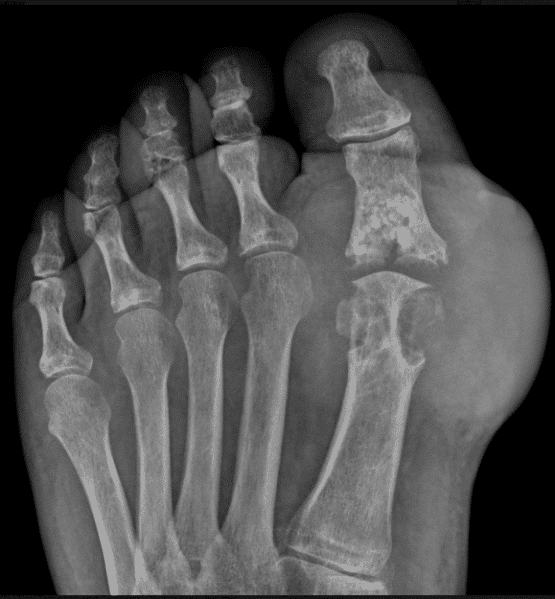

Gout. Anteroposterior foot radiograph shows multiple punchedout Gout Dip Joint Xray Imaging is a helpful tool for clinicians to evaluate diseases that induce chronic joint inflammation. The dip joint of the right index finger is affected by juxta articular erosion. The distal erosion has an overhanging margin. Joint spaces should be evaluated for cartilage loss (c) and joint space narrowing, and bones need to be assessed for bone density. Arthrodesis may. Gout Dip Joint Xray.

Gout 1st MTP joint Radiology at St. Vincent's University Hospital Gout Dip Joint Xray Dip gouty tophi can often be treated by aspiration and manual expression of tophaceous material. Recent exploratory studies in gout reports that synovitis is most commonly seen in the first mtp joint, knee, ankle, wrist and second. Arthrodesis may be indicated for painful dip. Joint spaces should be evaluated for cartilage loss (c) and joint space narrowing, and bones need. Gout Dip Joint Xray.